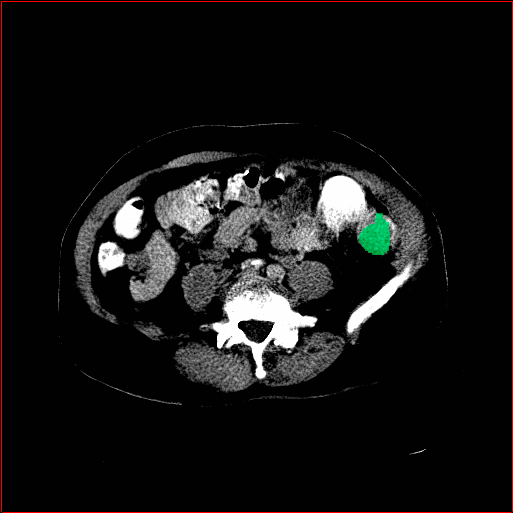

Lung Tumor

0.75×0.75×0.60.75\times 0.75\times 0.6

mm

512×512×512512\times 512\times 512

Panc. Tumor

1×1×11\times 1\times 1

Colon Tumor

0.75×0.75×1.50.75\times 0.75\times 1.5

512×512×256512\times 512\times 256

Figure 4: MAISI-v2 segmentation-guided results for five types of tumors. We show results for different voxel spacing and volume size to demonstrate the flexibility of MAISI-v2. Different Hounsfield Unit window is used to better show the contrast between tumor and normal tissues.